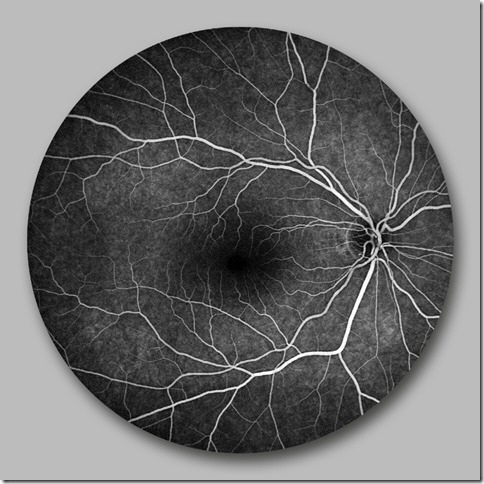

• Fluoreszenz Angiographie

ermöglicht eine detaillierte Aussage über den Durchblutungsgrad der Netzhaut und läßt neugebildete Gefäße sowie das Eindringen von Flüssigkeit aus den Blutgefäßen in die Netzhautschichten (Ödem) erkennen.